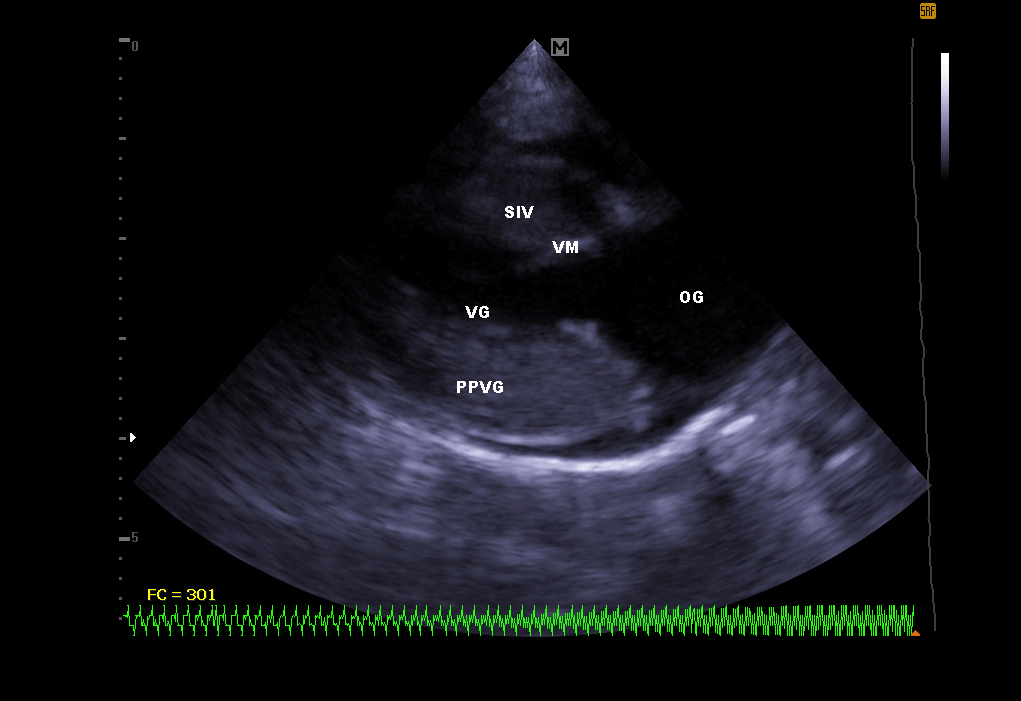

Elle permet de visualiser les différentes parties du cœur (parois, cavités, valvules) et de repérer d’éventuelles anomalies qui empêchent un fonctionnement cardiaque correct . En cas d’insuffisance cardiaque, l’échocardiographie permet aussi un suivi régulier de la morphologie cardiaque. Il est alors plus facile de réajuster le traitement mis en place.